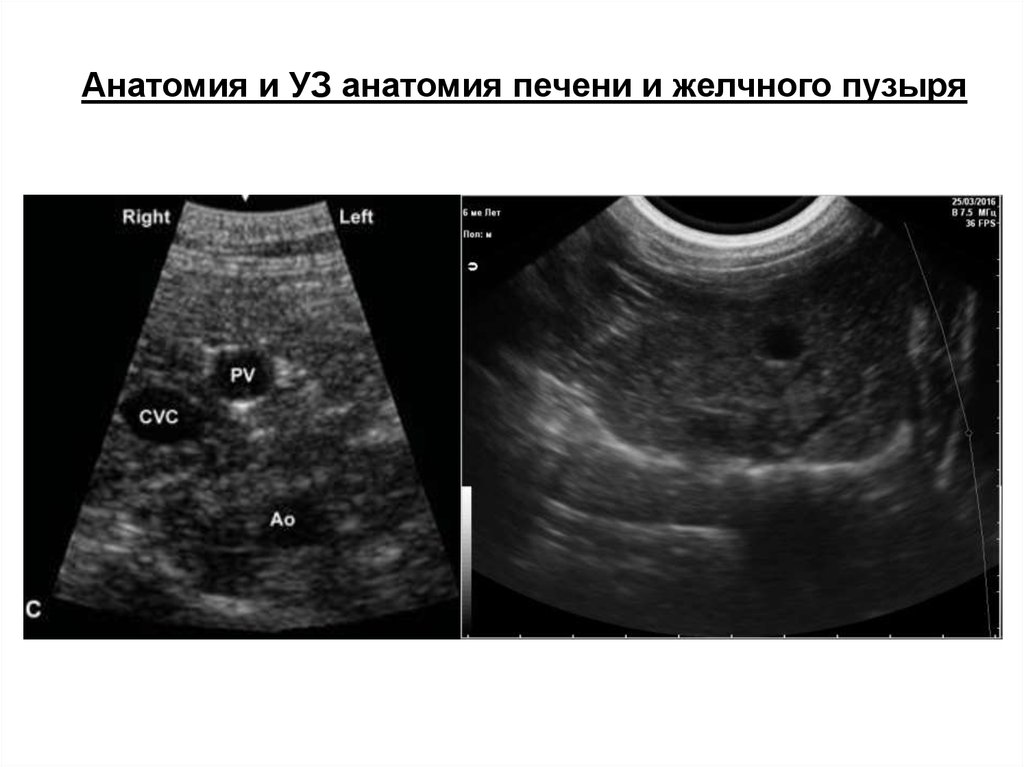

Анатомия и УЗ анатомия печени и желчного пузыря

Серповидная связка